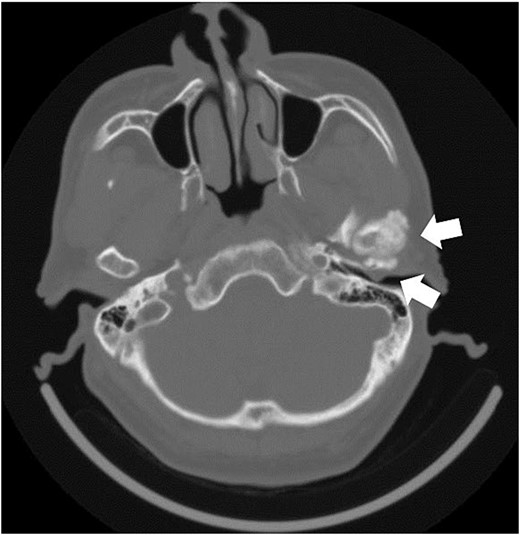

A 62-year-old man presented with a left external auditory canal obstruction and a smooth swelling on the anterior wall. Audiological exams showed no abnormalities, and no otorrhea was observed. Medical history included emphysema, duodenal cancer, and gastric ulcer. The patient was diagnosed with an external auditory canal cyst and underwent cystectomy at the Department of Otorhinolaryngology of our hospital in February 2017. Histopathological examination revealed a cystic lesion without epithelial lining, diagnosed as a ganglion-like lesion. In May of the same year, the swelling was observed again (Fig. 1). The patient was referred to our department for further investigation because computed tomography (CT) revealed enlargement of the left mandibular head (Fig. 2). Clinical findings at the time of consultation included symmetrical facial appearance and a maximum range of motion of 55 mm in the mandible. Upon opening the mouth, crepitus was observed in the left TMJ; however, no restriction of the lateral or anterior movement of the mandible or occlusal deviation was observed. There was no pain in opening the mouth or tenderness in the TMJ. The anterior wall of the left external auditory canal was swollen, with elasticity and no mobility. T2-weighted magnetic resonance imaging revealed an internal high-signal mass in the external auditory canal (Fig. 3).

Axial section image of bone conditions on contrast-enhanced CT. CT image shows enlargement of the left temporomandibular head and a mass in the external auditory canal.